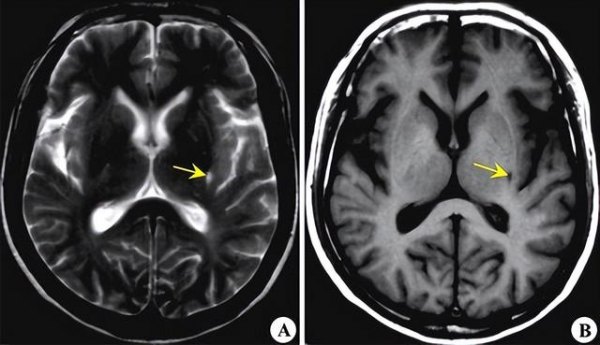

王大爷今年56岁了,他平时身体还不错。然而,最近一段时间,他总是感觉到头晕。刚开始的时候,他以为头晕是自己最近没有睡好的缘故,于是他就买了一点安眠药吃。不知不觉,三天过去了,王大爷头晕的症状并没有减轻。无奈之下,王大爷就去医院就诊了。

到了医院后,门诊医生在充分了解了王大爷的情况后,就给他测量了血压,其测量值为152/86mmHg。随后,王大爷又做了头颅CT检查,结果提示腔隙性脑梗死。